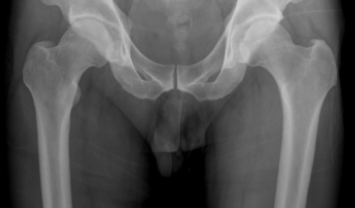

고관절은 골반과 대퇴골을 이어주는 관절입니다. 그래서 엉덩이관절, 엉덩관절 등 여러명칭으로 불리고 있습니다. 고관절이 불편하거나 통증이 있다면 하체를 움직이기에 불편함이 커집니다.